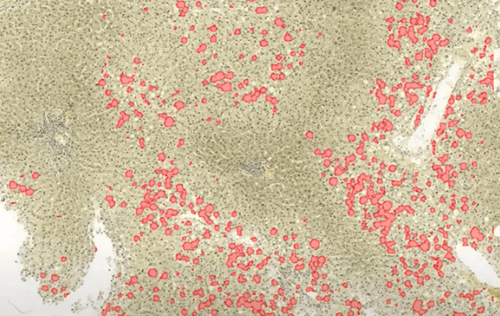

Case study: AI model can improve large droplet fat quantitation in liver pathology

Dr. Maxwell L. Smith from Mayo Clinic built an AI model to accurately estimate large droplet fat in liver sections prior to transplantation.